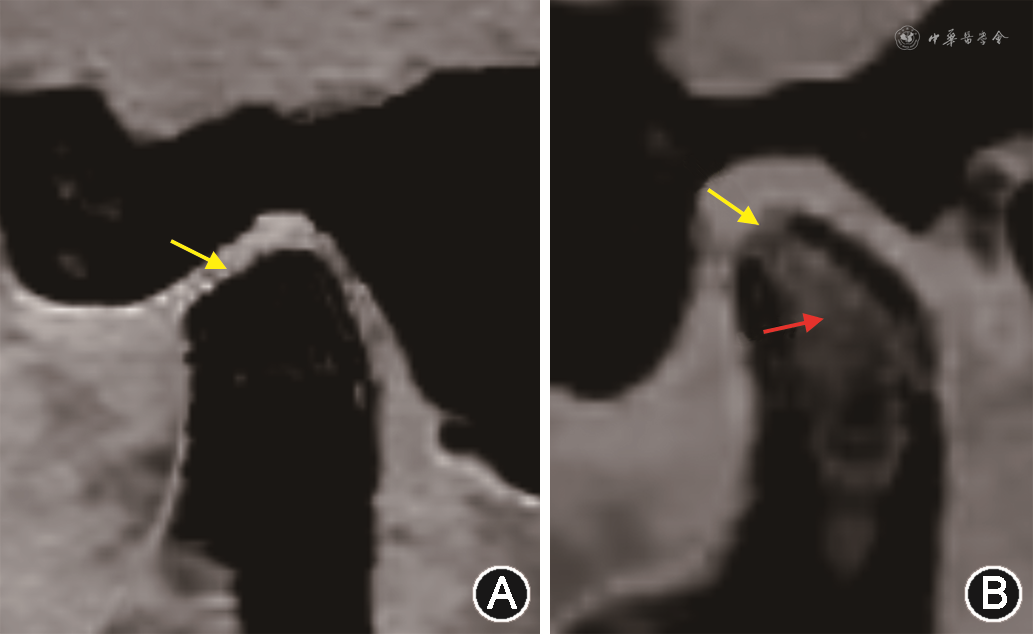

TMJ骨关节炎是严重的TMD之一,是一种进行性软骨退化、软骨下骨改建、滑膜炎和慢性疼痛为特征的退行性关节病,其特征性改变主要包括髁突扁平(图5A)、磨损(图5B)、骨赘及囊性变。钙抑制CT成像不仅可清晰显示髁突形态学改变,同时也可通过对骨质中钙的抑制显示骨髓水肿(图5B)、骨质磨损。